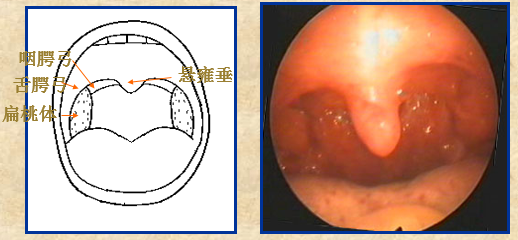

暴露咽峡,观察咽部形态变化、活动情况、粘膜色泽,湿润程度。同时检查舌腭弓、咽腭弓及两侧扁桃体,注意咽部有无充血、肿胀、隆起、干燥、脓痂、溃疡、假膜或异物等病变。

注意描述扁桃体的情况:隐窝口处有无分泌物、疤痕等。

检查咽后壁、咽侧壁、咽侧索,并嘱病人发“呵”一“呵”音,观察腭弓及软腭是否对称,活动有大障碍。

急性化脓性扁桃体炎:右扁桃体充血肿胀,有脓性分泌物。

扁桃体周围脓肿:左侧咽腭弓及扁桃体充血肿胀,有脓性分泌物附着。